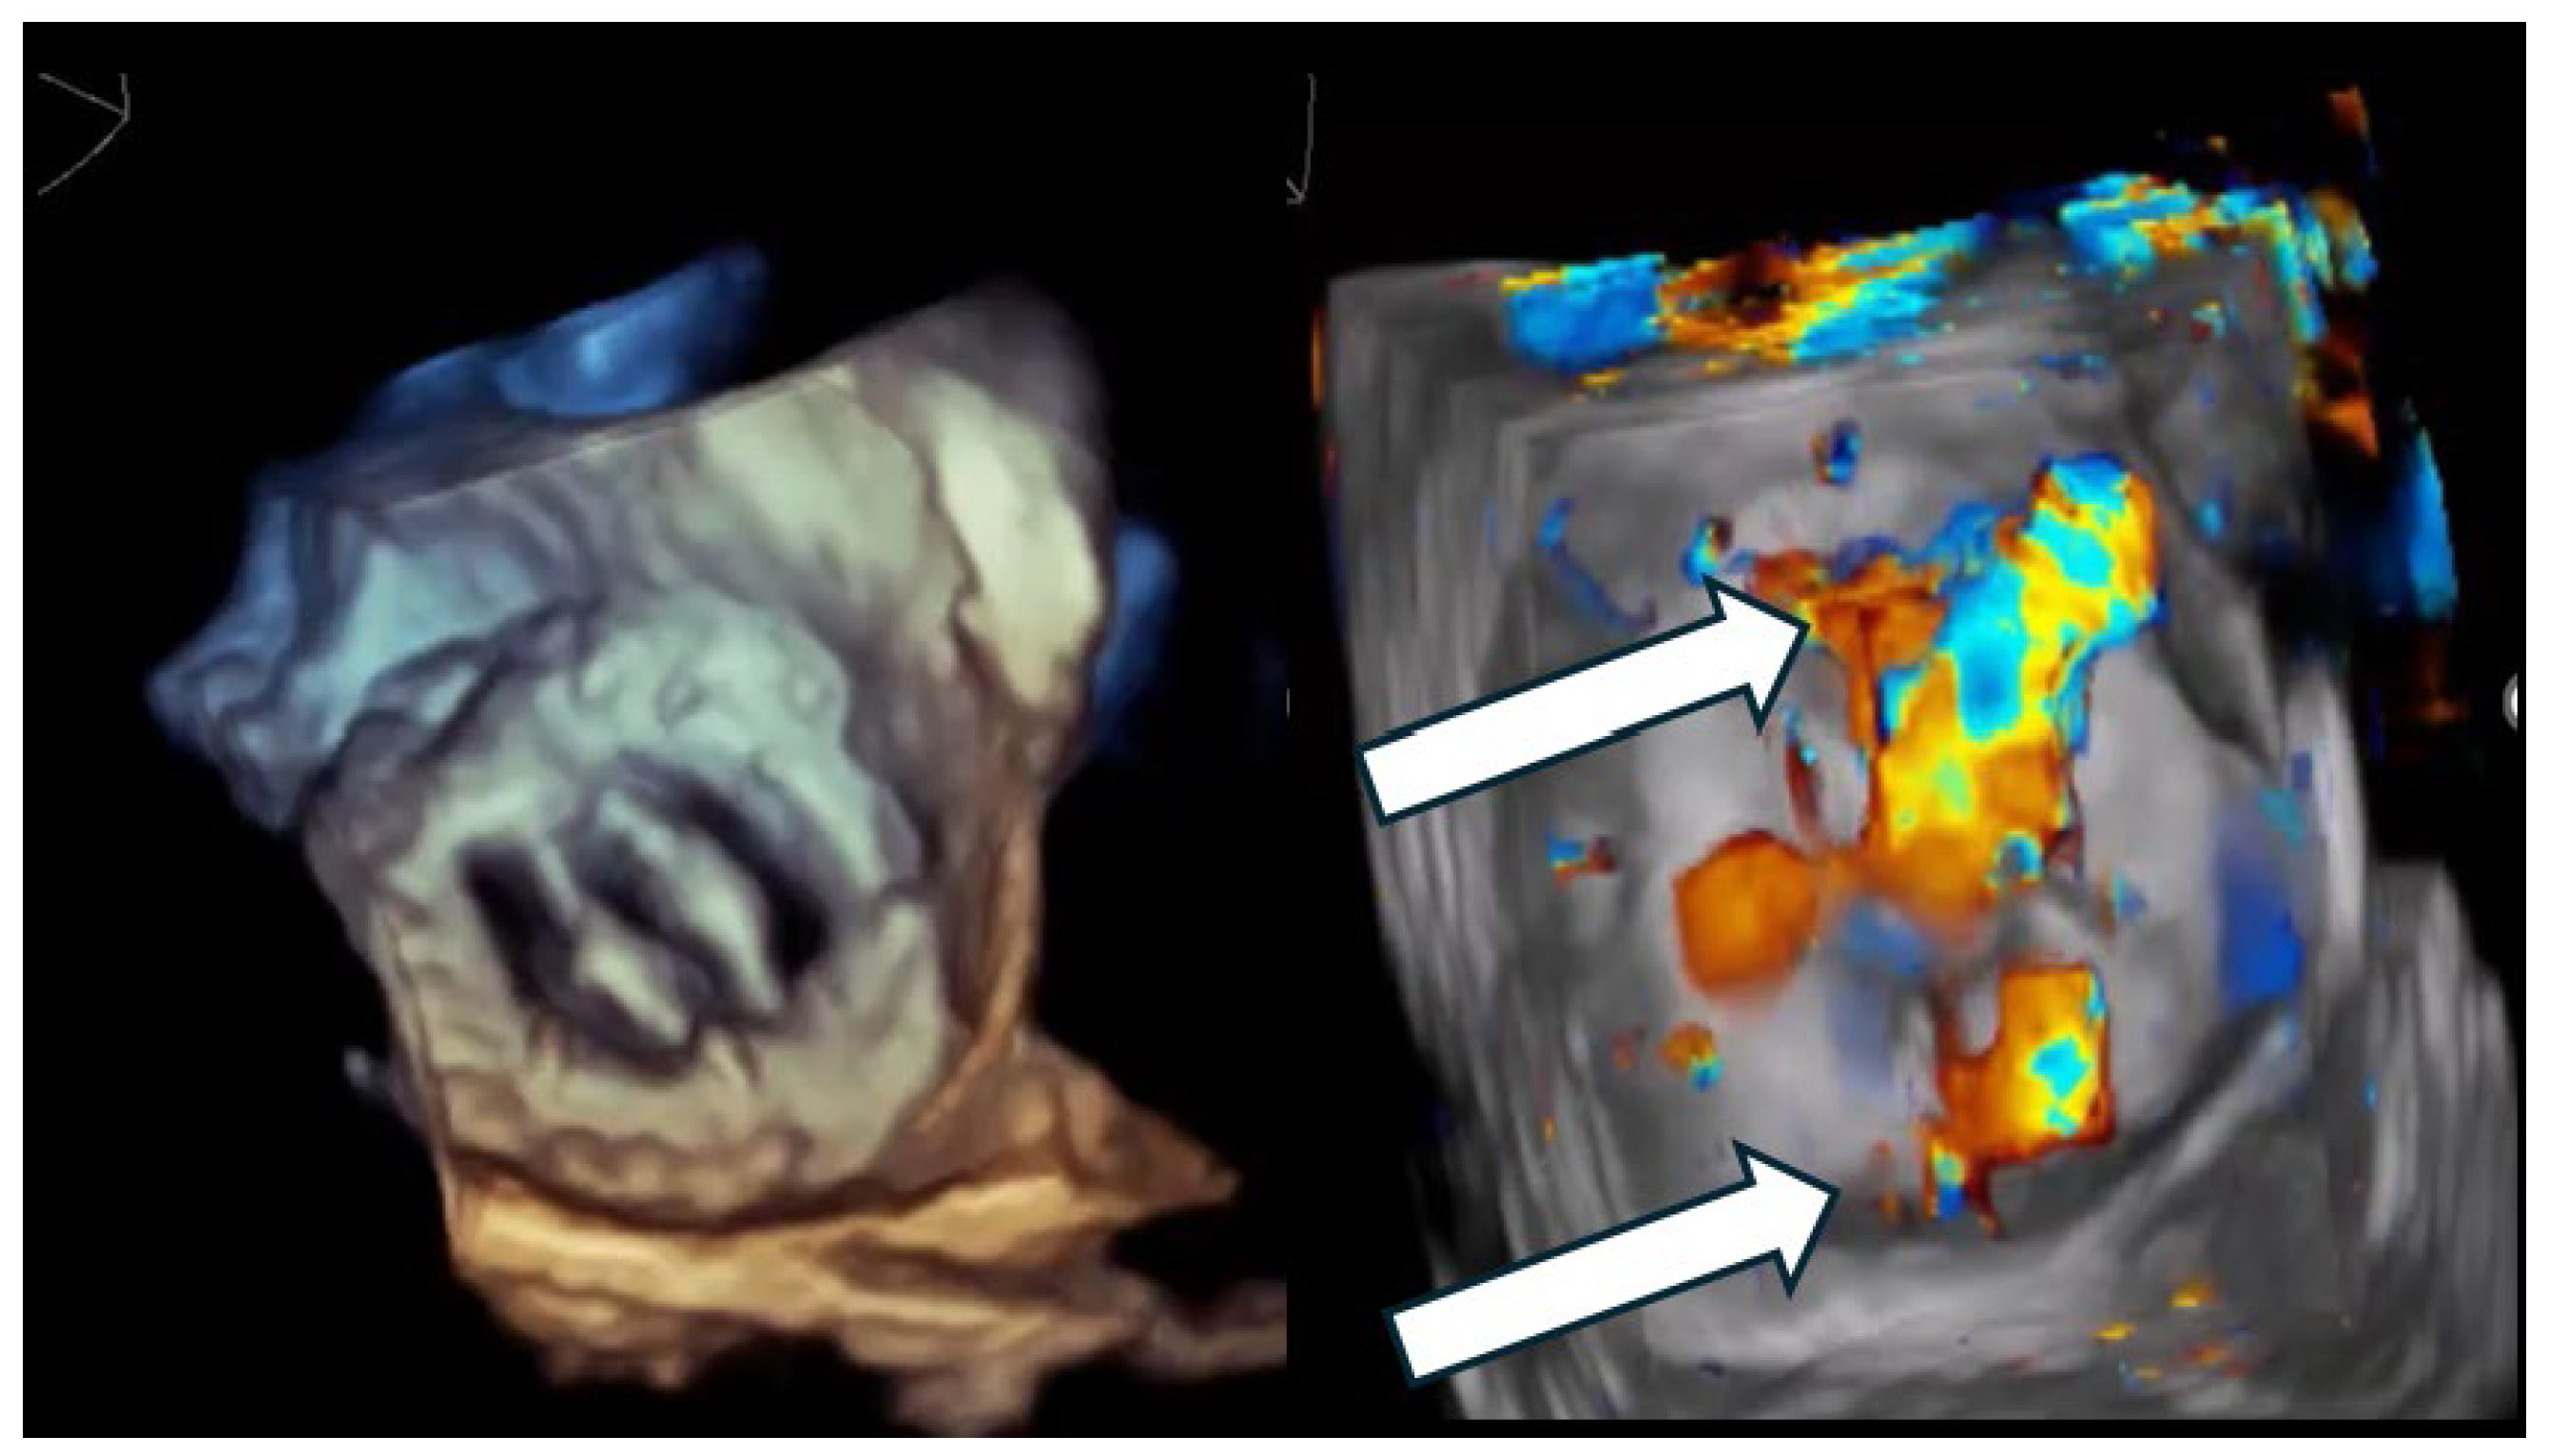

Figure 1.

Multi-orifice (two-hole) paravalvular leak demonstrated by three-dimensional transesophageal echocardiography. (Left panel): Three-dimensional transesophageal echocardiographic en-face reconstruction of the prosthetic valve illustrating the paravalvular region and surrounding annular anatomy. (Right panel): Corresponding three-dimensional color Doppler volume rendering demonstrating two spatially distinct paravalvular regurgitant orifices (arrows) along the prosthetic sewing ring. Each defect generates a separate high-velocity regurgitant jet, confirming the multi-orifice nature of the paravalvular leak rather than a single focal defect.